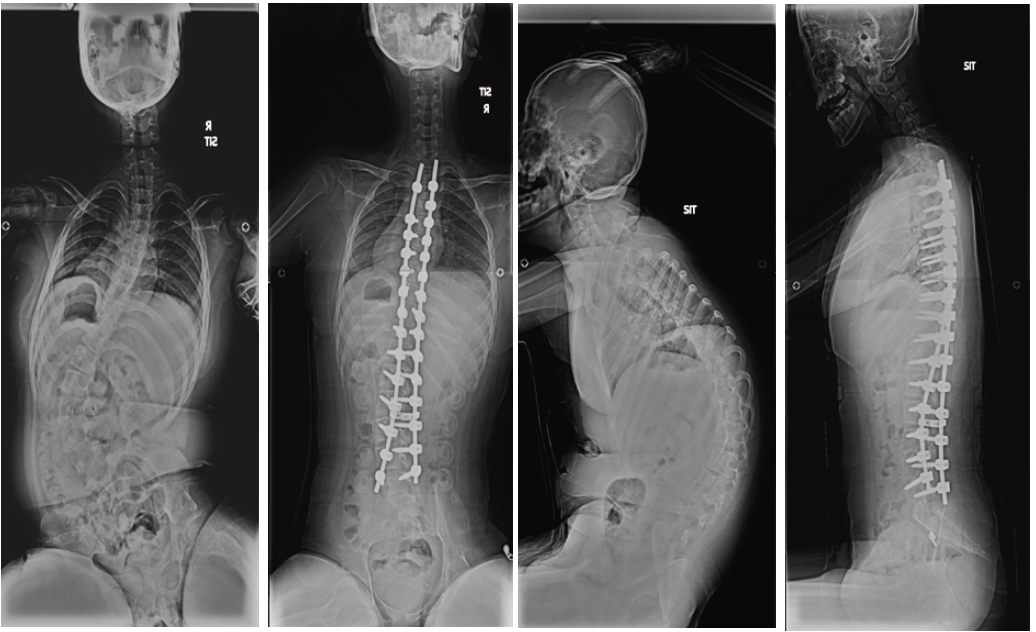

- 성장이 많이 남은 어린 아동에서 측만증이 심할 경우 그림과 같이 만곡의 위아래에만 일시적 고정 후 성장할 때 마다 강봉을 늘려 성장이 종료될 때까지 만곡의 진행을 방지합니다.

- 성장이 끝난 경우에는 교정이 필요한 모든 척추체에 고정을 하고 강봉을 이용하여 만곡을 교정하고 교정 후에는 골유합을 시행하게 됩니다.

- 허리쪽의 만곡이 심한 경우는 요추의 어느 부분까지 고정 할지가 중요합니다. 고정 범위가 길어지면 교정은 좋아 지지만 움직일 수 있는 허리의 운동 범위가 줄어듭니다. 보통 생활에는 지장이 없지만 허리의 운동 범위를 보존해 주는 것이 좋기 때문에 수술이 필요한 경우에는 만곡이 뻣뻣해 지기 전 적절한 어린 나이에 고정을 해주어 수술 범위를 필요한 부분만 하는 것이 좋습니다.

- 수술 후 어깨의 불균형이 예상되거나 상부 흉추의 만곡이 크고 강직된 경우 상부 흉추의 만곡을 수술에 포함하기도합니다. 목 아래까지 수술이 필요합니다.

- 수술 시 중요한 것은 만곡의 교정과 함께 머리-어깨-골반의 균형을 맞추어 주는 것입니다